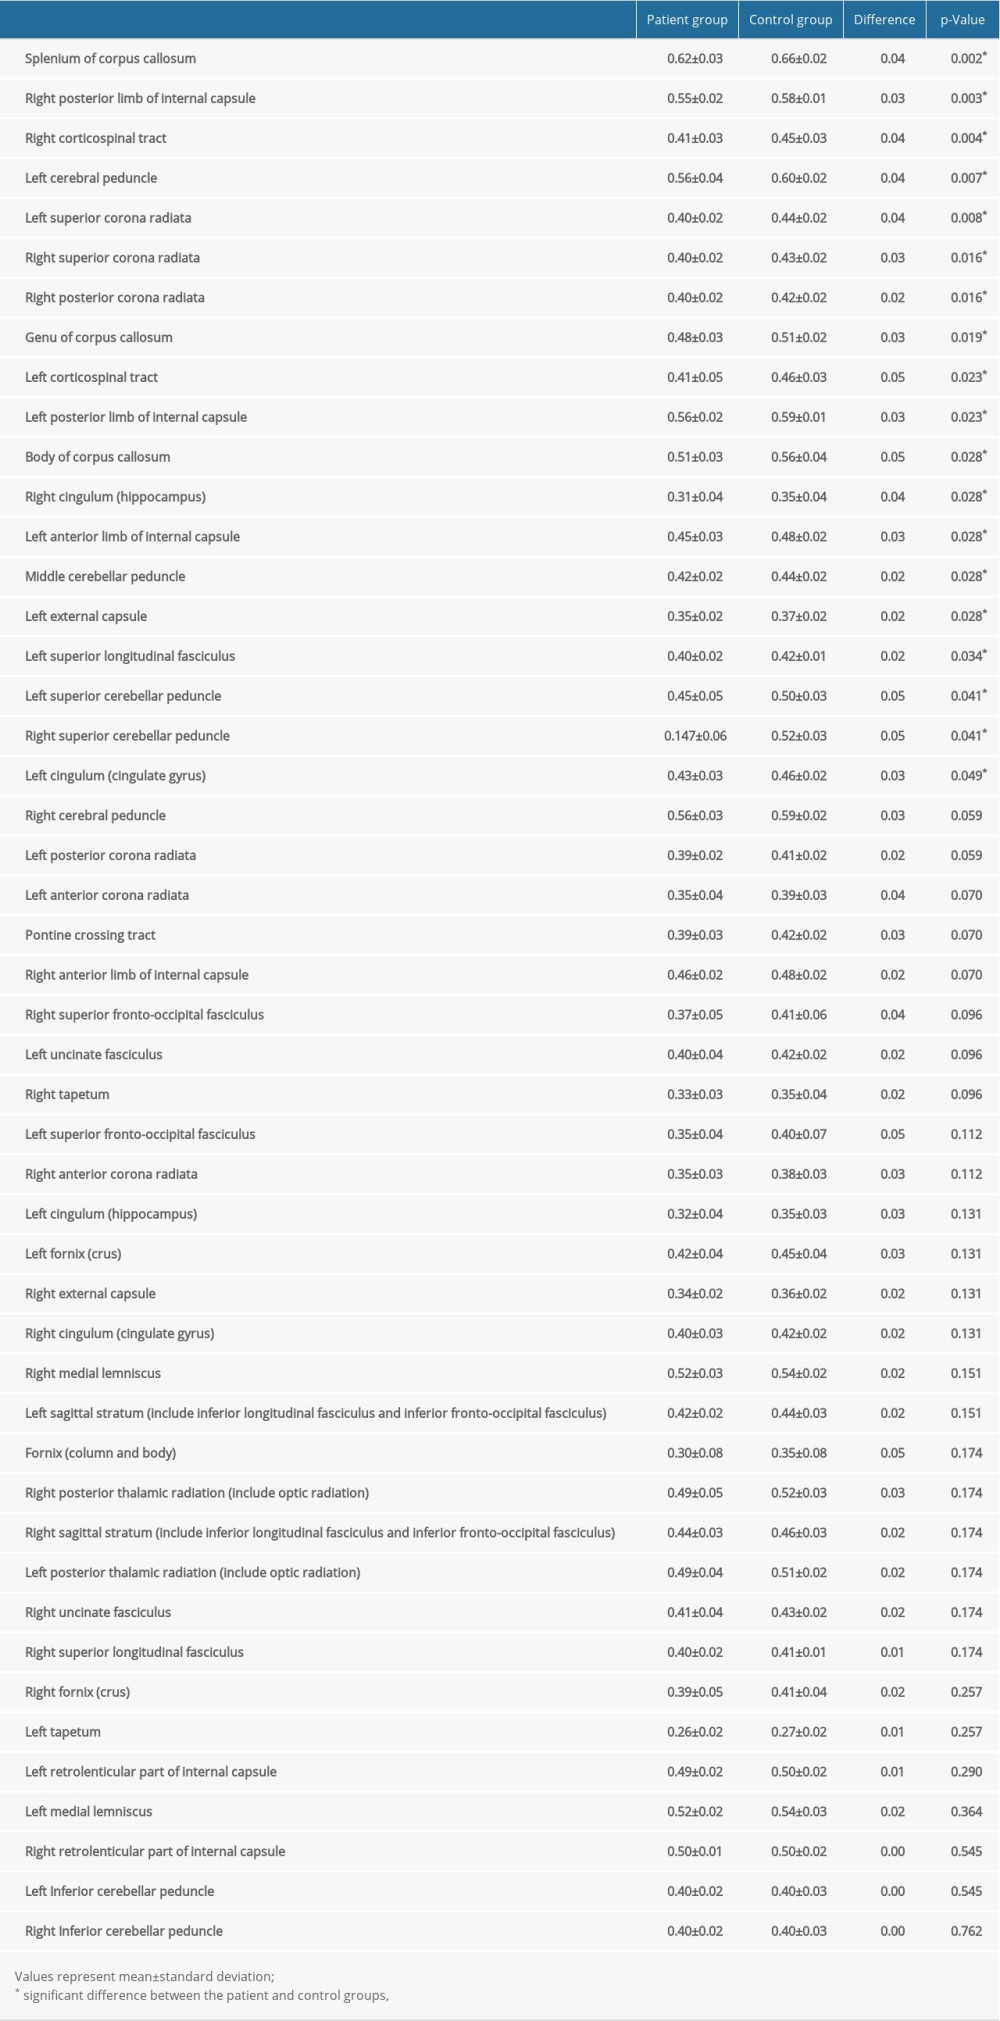

RESULTS: The fractional anisotropy values for 19 of 48 regions of interest showed significant divergences (P<0.05) between the patient group and control group. The regions showing significant differences included the corpus callosum and its adjacent neural structures, the brainstem and its adjacent neural structures, and the subcortical white matter that passes the long neural tract.

The voxel-wise FA values’ differences between the patient and control groups are listed in Table 2 and, all of the ROIs are presented in ascending order, beginning with the ROI with the lowest

The current study investigated microstructural differences in the subcortical white matter of the patient and control groups and obtained the following results: 1) FA values of the patient group were lower than those of the control group in 19 of the 48 white matter ROIs; 2) the ROIs with the lowest ratios for the FA values between the patient and control groups were associated with the corpus callosum and its adjacent neural structures (the corpus callosum and the cingulum), the brainstem and its adjacent neural structures (the cerebral peduncle, the superior and middle cerebellar peduncle), the subcortical white matter that passes the long neural tracts (the internal capsule, the corona radiata, the corticospinal tract, the external capsule, and the superior longitudinal fasciculus).

The FA value, which reflects the grade of water diffusion’s directionality and represents the integrity of white matter (eg, indicative of axon diameter, fiber density, and myelination), used to assess white matter status [24–26]. A reduced FA value indicates decreased microstructural integrity of the neural structure of interest [24–26]. Our results show that 19 of the assessed 48 ROIs in the patient group had lower mean FA values than those of the control group, suggesting the existence of neural injuries in these 19 white matter areas. In addition, the 19 ROIs (the corpus callosum, the cingulum, the superior cerebellar peduncle, the middle cerebellar peduncle, the cerebral peduncle, the internal capsule, the corona radiata, the corticospinal tract, the external capsule, and the superior longitudinal fasciculus) showing significant differences between the patient and control groups are consistent with the brain areas vulnerable to DAI [40–42]. DAI can be reflective of a widespread traumatic injury such as that associated with fast acceleration – deceleration of the head in which the shearing forces lead to mechanical axonal damage [40]. Many previous studies have reported that the common locations for DAI are the corpus callosum (especially the splenium), the subcortical white matter, and the brainstem [40–42]. In addition, injuries to several neural tracts, such as the cingulum, the corticospinal tract, the cerebellar peduncle, the superior and inferior longitudinal fasciculus, and the fornix, have also been detected in DAI patients by using DTT [15–23]. DAI is the chief cause of morbidity and mortality in traumatic brain injury patients [40]. Such patients frequently fall into a coma from the collision time, and survivors usually have severe disabilities. Based on our results, traumatic SAH patients appear to be accompanied by DAI; thus, traumatic SAH could be an indicator of the presence of severe brain injuries related to acute or excessive mechanical forces.

Table 1. Demographic characteristics for the patient and control groups. Table 2. Results from the region of interest-based analysis of fractional anisotropy values of the patient and control groups.

Table 2. Results from the region of interest-based analysis of fractional anisotropy values of the patient and control groups. Table 1. Demographic characteristics for the patient and control groups.

Table 1. Demographic characteristics for the patient and control groups. Table 2. Results from the region of interest-based analysis of fractional anisotropy values of the patient and control groups.

Table 2. Results from the region of interest-based analysis of fractional anisotropy values of the patient and control groups. In Press